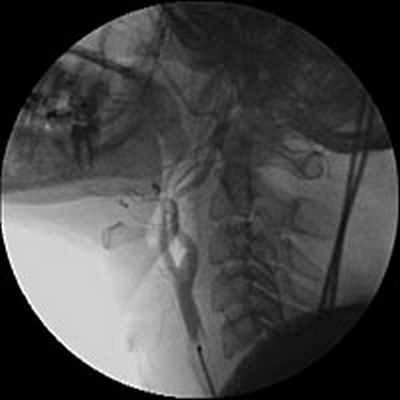

С целью уточнения особенностей кровоснабжения опухоли, а также решения вопроса о возможной эмболизации питающих опухоль сосудов была выполнена ангиография дуги аорты и брахиоцефальных артерий. При ангиографическом исследовании было выявлено слабо васкуляризованное образование, вызывающее перегиб левой внутренней сонной артерии в первом сегменте (рис.3).

Учитывая отсутствие крупных питающих опухоль сосудов, селективная эмболизация не выполнялась.

Рис. 3. Ангиография дуги аорты и брахиоцефальных артерий